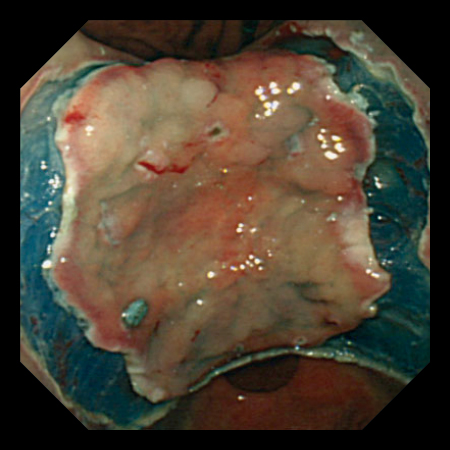

EMR

ESD